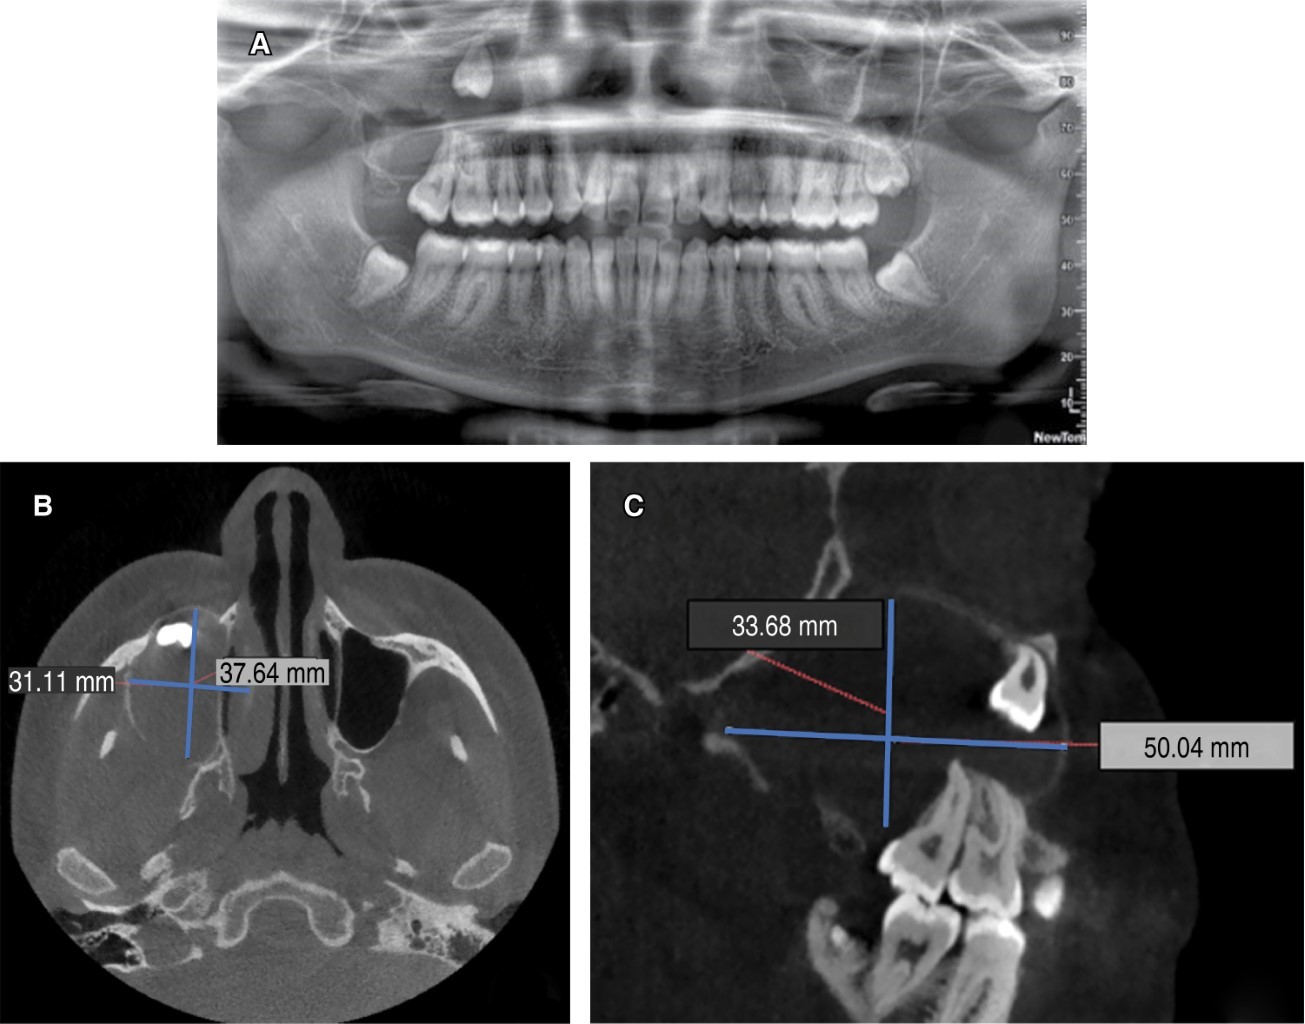

Se presentó paciente femenino de 19 años de edad a la Clínica de Cirugía Oral y Maxilofacial, de la División de Estudios de Postgrado e Investigación (DEPeI) de la UNAM, para la extracción de sus terceros molares; sin antecedentes de importancia para su tratamiento. En la ortopantomografía se observa el tercer molar superior derecho (OD 18) desplazado hasta piso de órbita ipsilateral, con una zona radiolúcida asociada a la corona del mismo, la cual ocupa todo el seno maxilar y se extiende hasta la tuberosidad del mismo lado, midiendo aproximadamente 3.3 × 5 cm, mientras que en la tomografía (cone beam) se observó la estrecha relación entre el ápice del tercer molar con el piso de órbita (Figura 1). Se inició con una punción exploratoria y se observa contenido amarillento compatible con queratina. Luego, se realizó biopsia incisional de la lesión y se extrajo el tercer molar en relación para estudio histopatológico. Se colocó drenaje utilizando una sonda Foley No. 18 y se indicó higiene estricta del mismo (Figura 2).

Figura 2

Figura 4